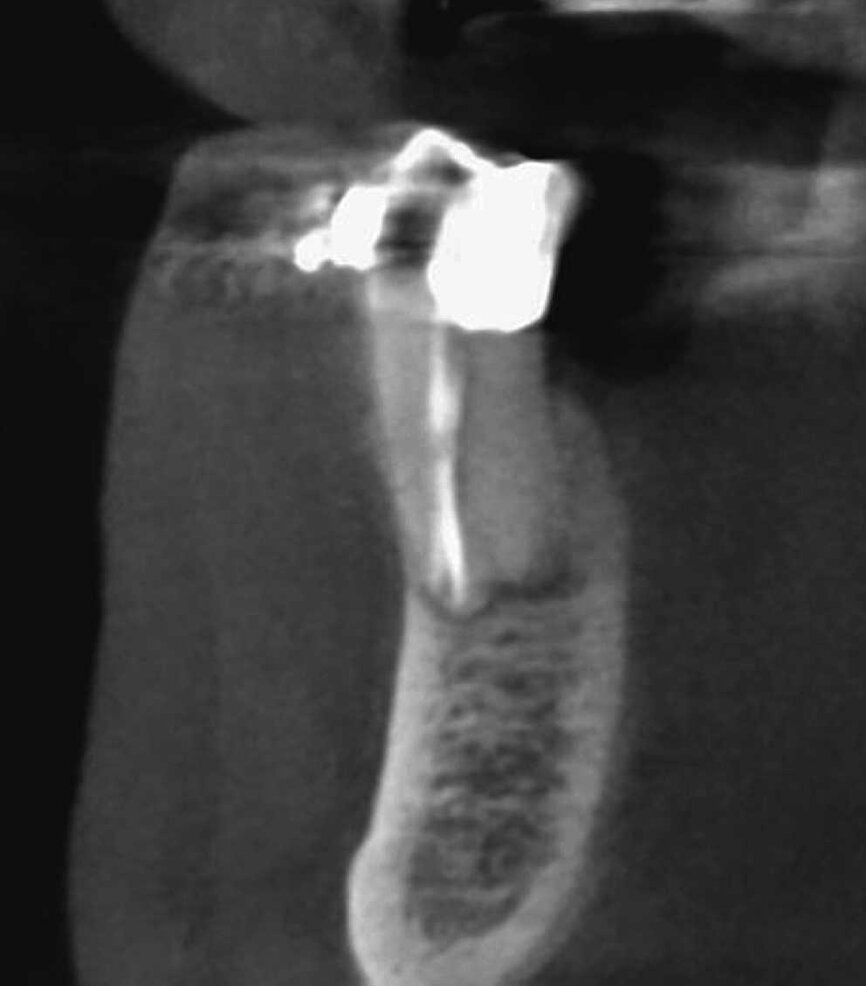

Le cas avec lequel je souhaite commencer mon exposé clinique est un exemple parfait de la difficulté à définir l’origine des symptômes d’un patient, par l’examen d’une simple radiographie intraorale. Non seulement l’examen 2D ne permet pas d’établir avec certitude la présence d’une lésion, mais surtout, il est impossible d’en déterminer la taille, la morphologie et le type. Au contraire, une analyse de l’imagerie 3D offre une image claire de la situation clinique. Chez ce patient, les coupes coronales et sagittales révèlent la présence d’une importante lésion s’étendant de l’apex de la racine mésiale de cette molaire jusqu’à la zone de furcation, tandis que les coupes axiales nous permettent d’analyser précisément l’anatomie endodontique et, en particulier, la forme de la racine mésiale, qui apparaît fusionnée avec la racine palatine. Un panorama complet du cas peut donc guider le processus de décision et orienter le plan de traitement vers une modalité bien précise de traitement (Figs. 1–4).